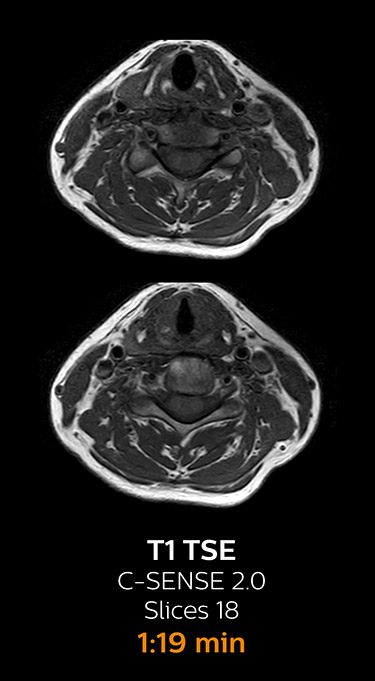

With Compressed SENSE, the scan time for the routine cervical spine examination at KNC was reduced from 13:11 to 9:52 minutes, which corresponds to 25% reduction.

MRI examination of the cervical spine with Compressed SENSE

Ingenia 3.0T CX

Scan time 9:52 min. (was 13:11 min. without Compressed SENSE)